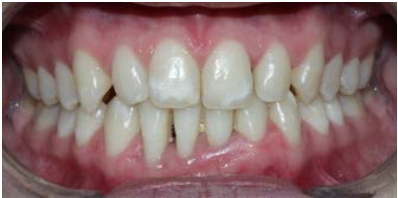

A 24- year-old patient was referred to the periodontist by a general dentist; the main concern of the dentist was the periodontal health of the right mandibular incisors of the patient, since she requested an orthodontic treatment. During the periodontal examination, the lower-left incisors (4.1and 4.2) were diagnosed with Cairo’s RT3 gingival recession, with a thin phenotype, type II mobility, and dental extrusion (Figure 1). The patient was referred to the orthodontist for the latter to evaluate the occlusal trauma and extrusion of the incisors involved. At this point, it was decided to thicken the surrounding gingival phenotype of teeth 4.1 and 4.2 before starting orthodontic therapy.

Figure 1 Initial clinical examination. A remarkable thin phenotype and RT3. sourounding teeth 4.1 and 4.2 is shown. Both teeth were also associated to type II mobility and dental extrusion.